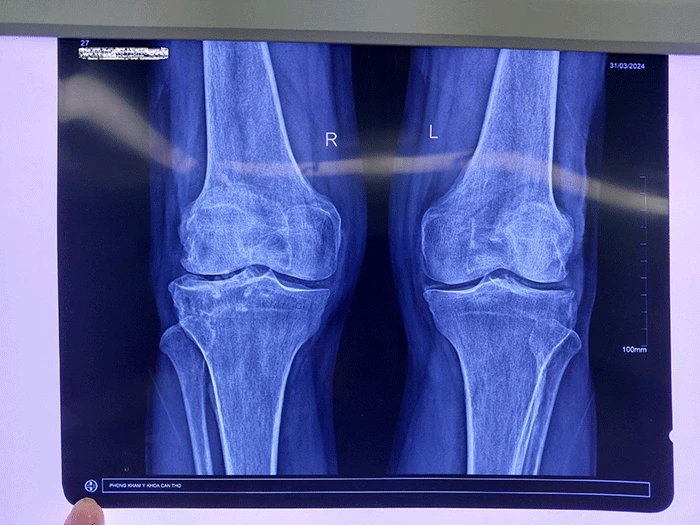

Gần đây, cụ H đến Bệnh viện (BV) Đại học Nam Cần Thơ thăm khám. Kiểm tra các dấu hiệu lâm sàng và kết quả xét nghiệm và hình ảnh, bác sĩ chẩn đoán bệnh nhân bị thoái hóa khớp gối. Sau hội chẩn trên cơ sở tiền sử bệnh, hồ sơ bệnh án bệnh nhân, các bác sĩ khoa Ngoại tổng hợp BV chỉ định phẫu thuật nội soi khớp gối cho cụ H.

Quá trình nội soi, bác sĩ phát hiện bệnh nhân bị sụn xương thoái hóa (giống sỏi) do thoái hóa khớp gối và canxi hóa tạo thành gai xương lâu năm. Đây là nguyên nhân khiến bệnh nhân đau, gặp khó khăn trong vận động. Ê-kíp đã thực hiện phẫu thuật nội soi, cắt lọc mô viêm cũng như lấy bỏ sạn khớp. Sau một ngày can thiệp, bệnh nhân hết đau, có thể sinh hoạt, đi lại và vừa được xuất viện.